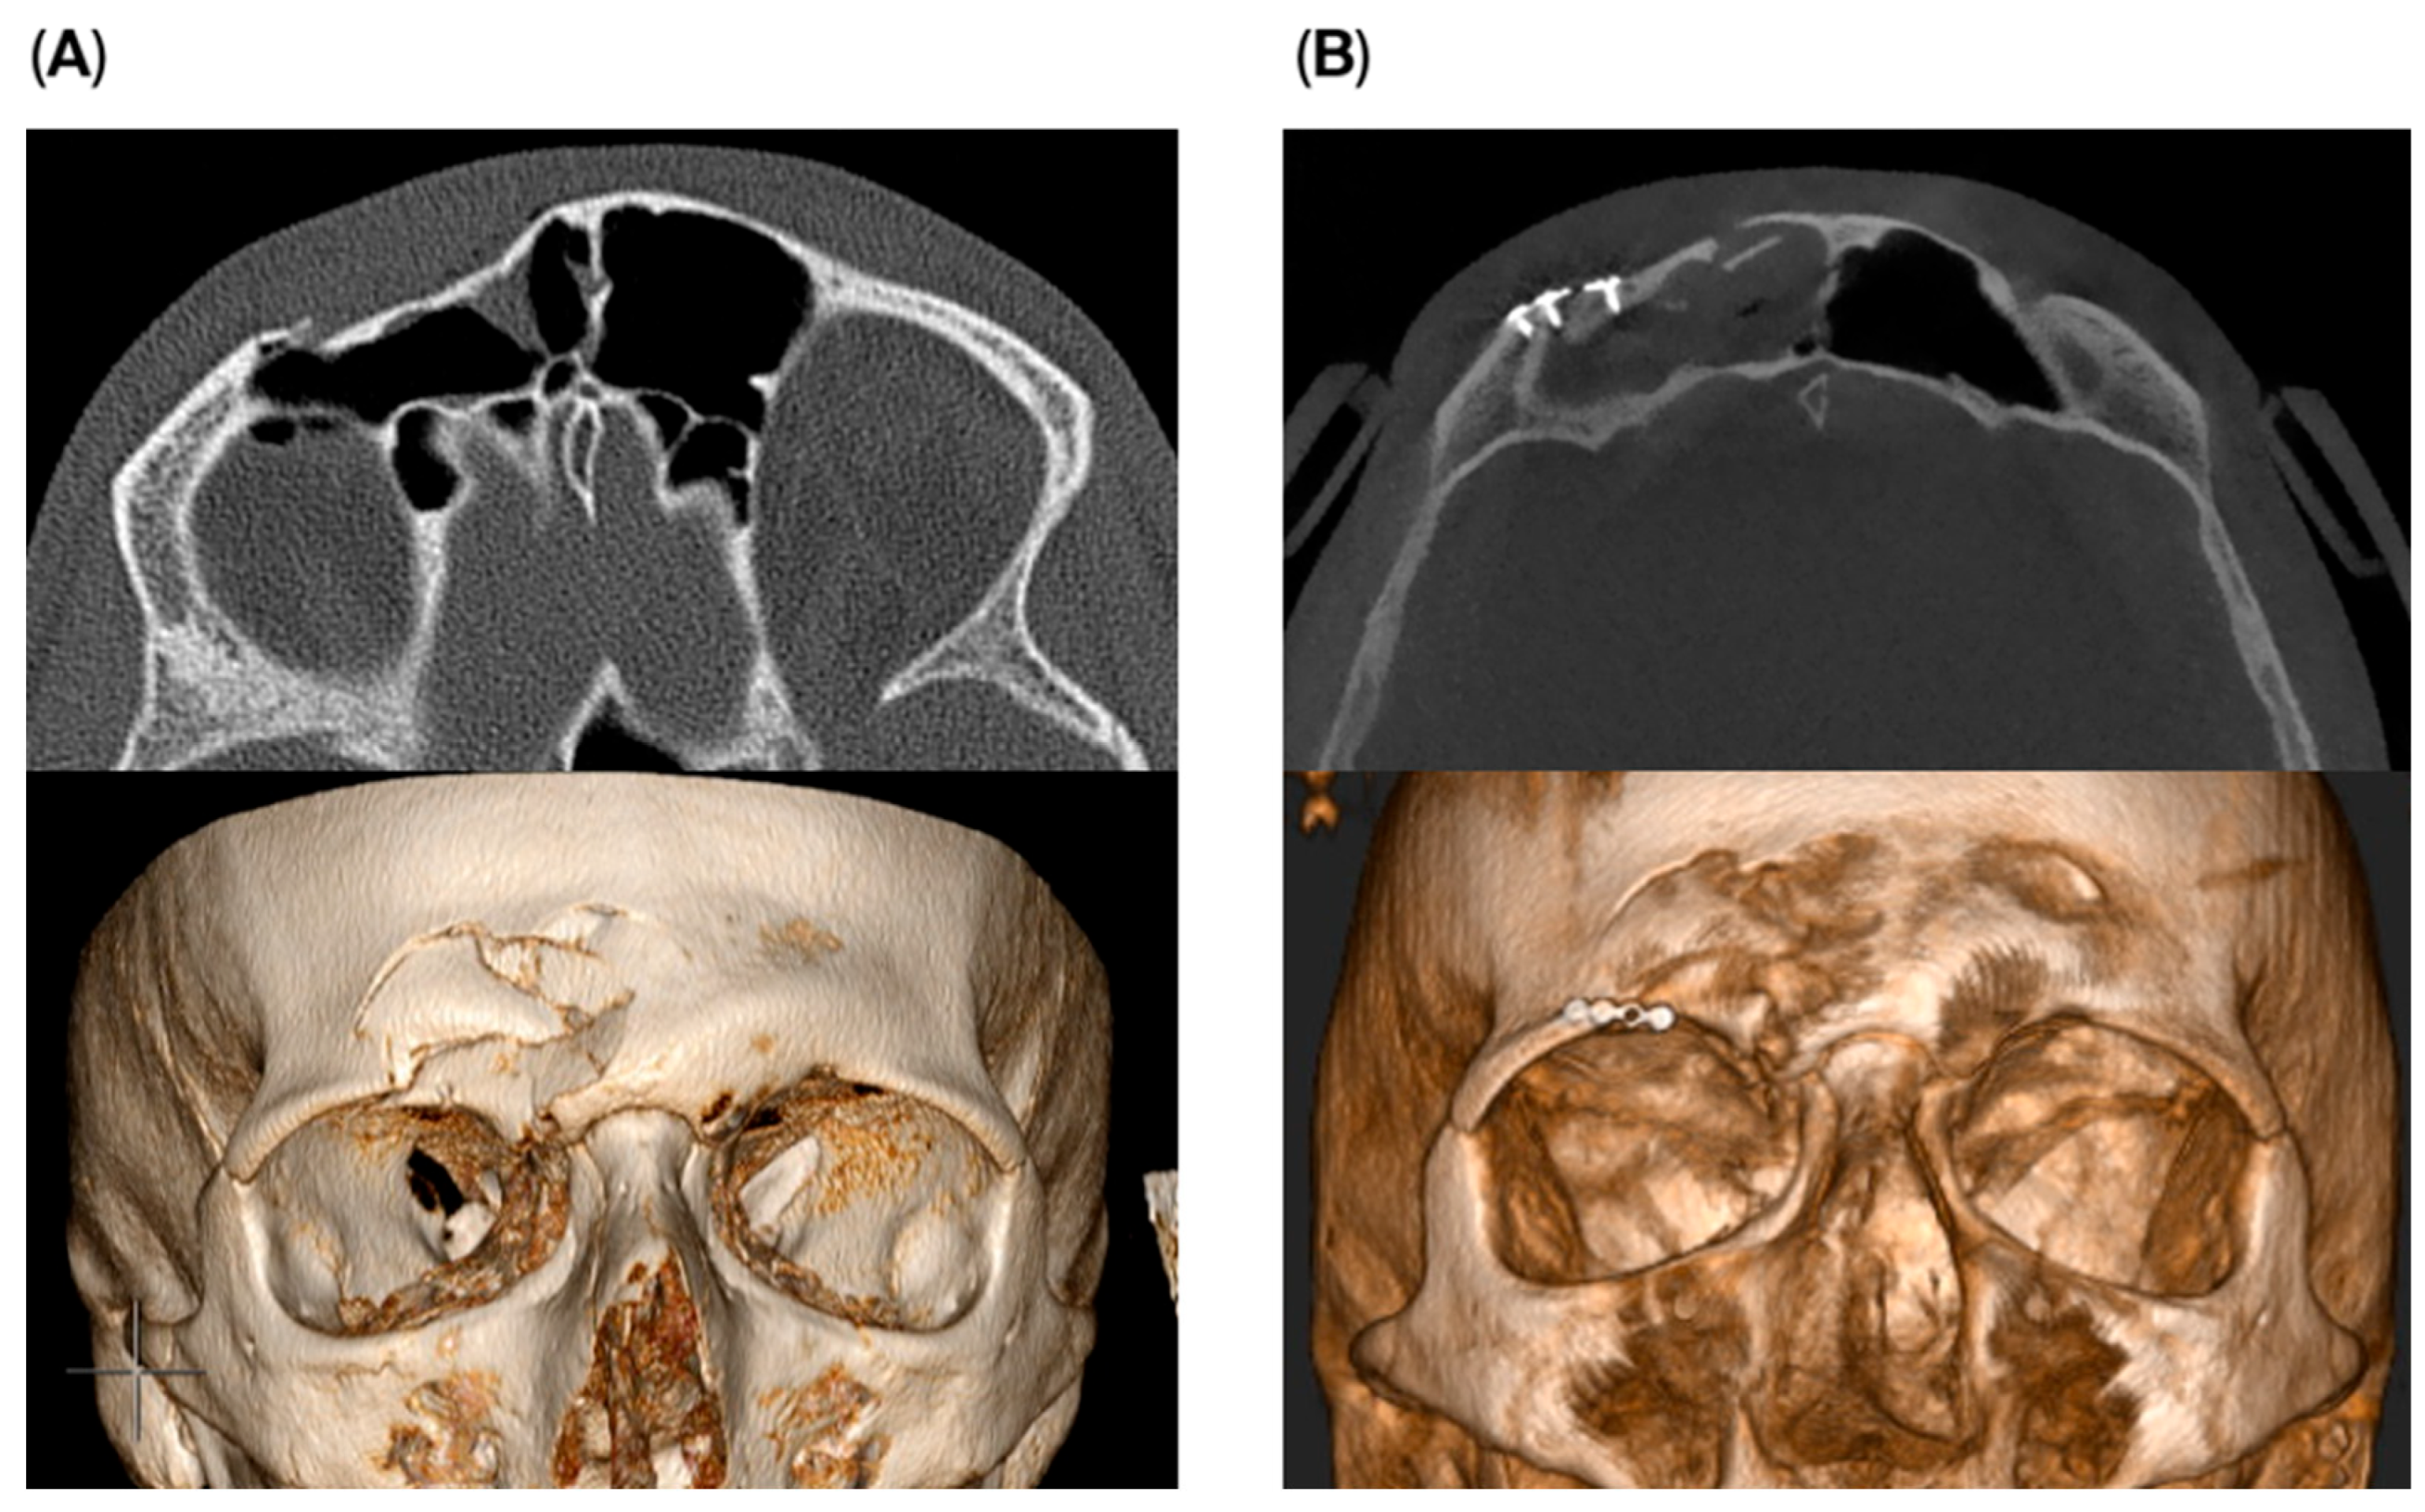

Among patients treated via the endoscopic transorbital approach, four experienced temporary hypoesthesia of the supraorbital nerve one week postoperatively. All cases resolved within a few weeks. One patient developed temporary partial ptosis of the upper eyelid, which resolved approximately four weeks after surgery. In another patient, a residual defect of the anterior wall remained visible as a small external ‘dimple’. Although an additional corrective procedure was proposed, the patient opted against further intervention. All remaining patients achieved satisfactory fracture reduction with no visible residual defects (Figure 3).

Figure 3. Pre- (A) and postoperative (B) images of a patient treated using the endoscopic transorbital approach.